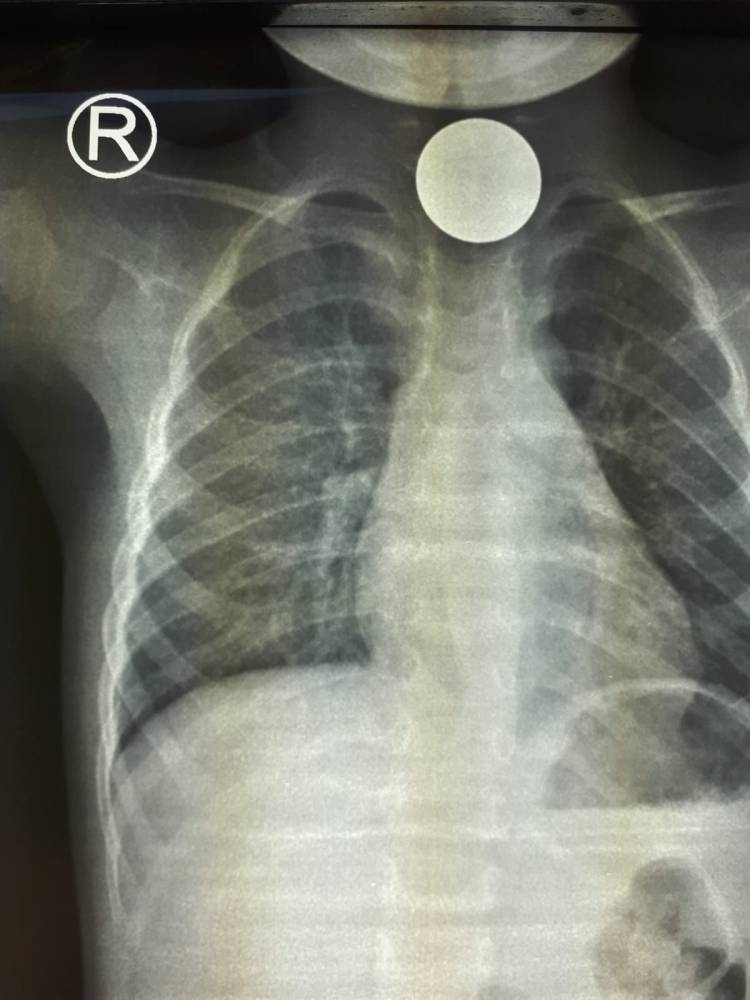

استخرج فريق طبي بمستشفى رابغ العام قطعة معدنية من بلعوم طفل يبلغ من العمر عامين خلال عملية لم تستغرق أكثر من 10 دقائق.

وأوضحت «صحة جدة» أن الطفل قَدِم إلى طوارئ المستشفى وهو يشكو ابتلاع جسم غريب (قطعة نقود معدنية) كانت قد علقت في منطقة البلعوم؛ مما تسبب في اختناق وعدم قدرة على البلع؛ إذ قرر الطاقم الطبي إجراء عملية عاجلة بالمنظار لإزالة الجسم الغريب، إذ تبين وجود قطعة معدنية نقدية، وقد كُللت العملية بالنجاح دون حدوث مضاعفات، وغادر الطفل المستشفى وهو بصحة جيدة.